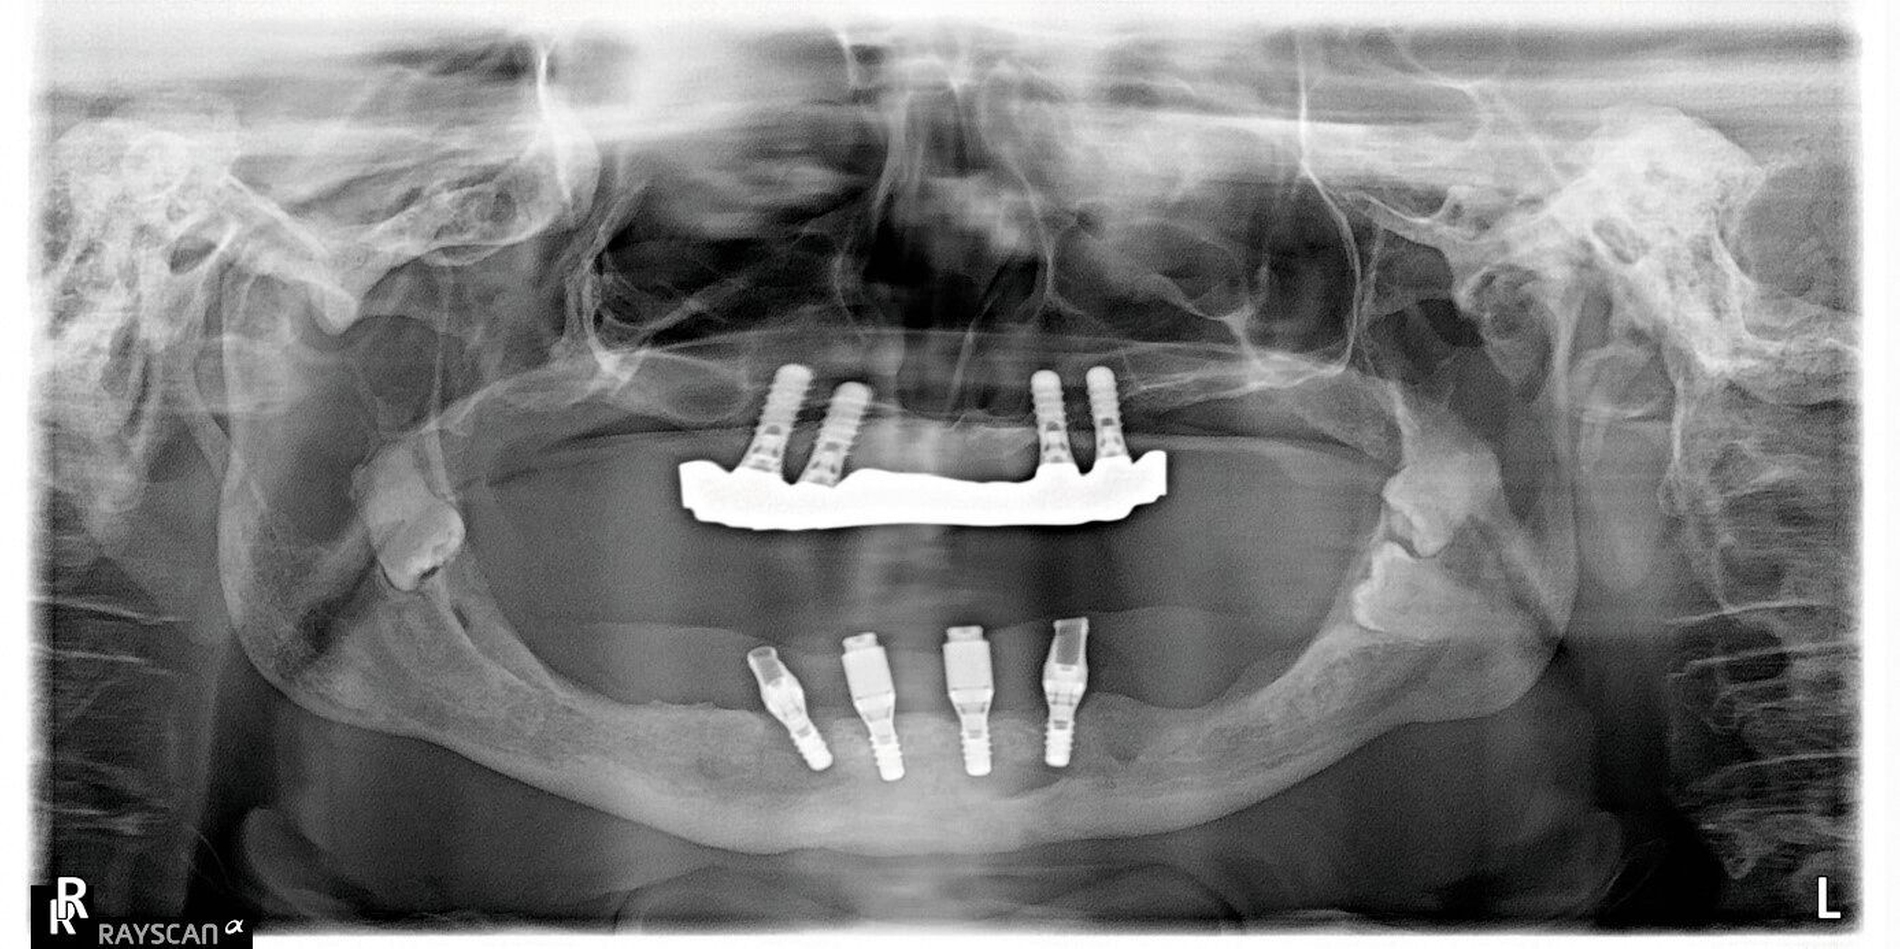

In der Panoramaschichtaufnahme sind beidseits in den aufsteigenden Ästen des Unterkiefers verlagerte Zähne 39, 38, 48 und 49 zu erkennen (Abbildung 1). Der anteriore Alveolarfortsatz erscheint in der zweidimensionalen Projektion ausreichend hoch zu sein.

Zum Ausschluss einer Kieferwinkelfraktur bei verlagertem, doppelt angelegtem und infiziertem Weisheitszahn sowie zur Planung der späteren Rekonstruktion wird ein DVT angefertigt (Mesantis Berlin), das eine dehiszente knöcherne Abgrenzung zum pericoronalen Raum 48–49 im Kieferwinkel rechts mit kariösem Zahn 48 und Konkrement zeigt (Abbildung 4).

Nebenbefundlich ist für die spätere prothetische Rehabilitation in den sagittalen Schnitten zu erkennen, dass sowohl die scheinbare Knochenhöhe des anterioren Alveolarfortsatzes in Projektion der zweidimensionalen Aufnahme als auch die vermeintlich klinisch nutzbare Breite durch eine ‚bandnudelartige‘ diagonale Verdrillung der schmalen Knochenspange in beiden Ebenen nur vorgetäuscht sind (Abbildung 5).